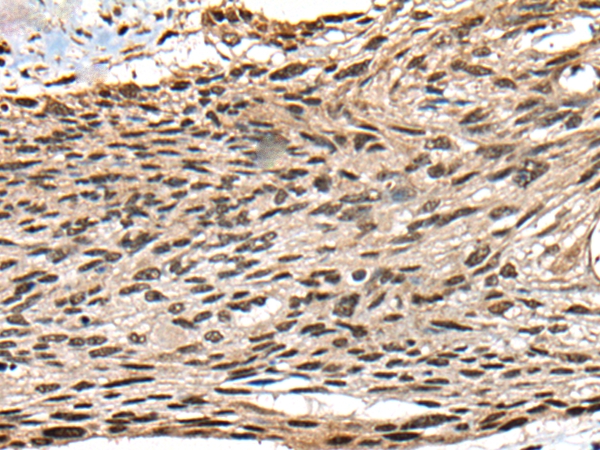

IHC (Immunohistochemisry)

(The image on the left is immunohistochemistry of paraffin-embedded Human liver cancer tissue using 46425(CCNB1IP1 Antibody) at dilution 1/25, on the right is treated with fusion protein. (Original magnification: x200))